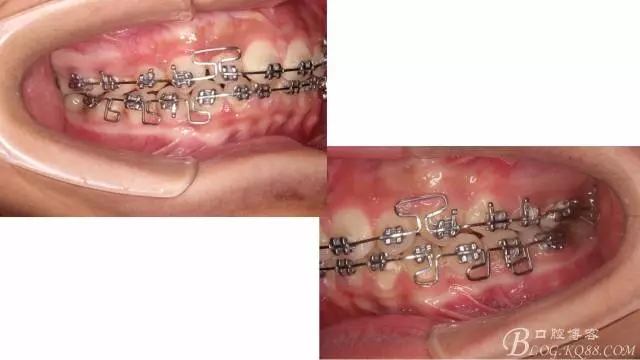

佩戴三個月的FR2, 效果奇佳!前牙基本達到淺覆蓋,淺覆合!接下來進入二期直絲弓固定正畸,排齊階段!

接下來盡管配合些雙側(cè)后牙對角牽引,咬合關(guān)系依,不盡人意。

下頜配合多曲方絲,三角牽引,調(diào)整咬合。

中線不齊,咋辦?繼續(xù)哄哄患者配合,2牽+斜牽。

努力沒有白費,中線基本對齊!